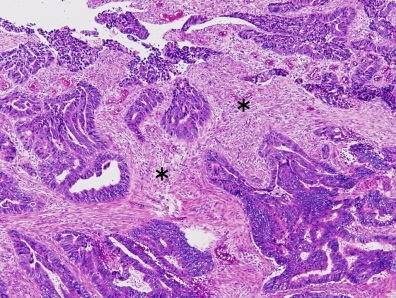

Colorectal carcinoma with desmoplastic reaction (*)

Dirty necrosis